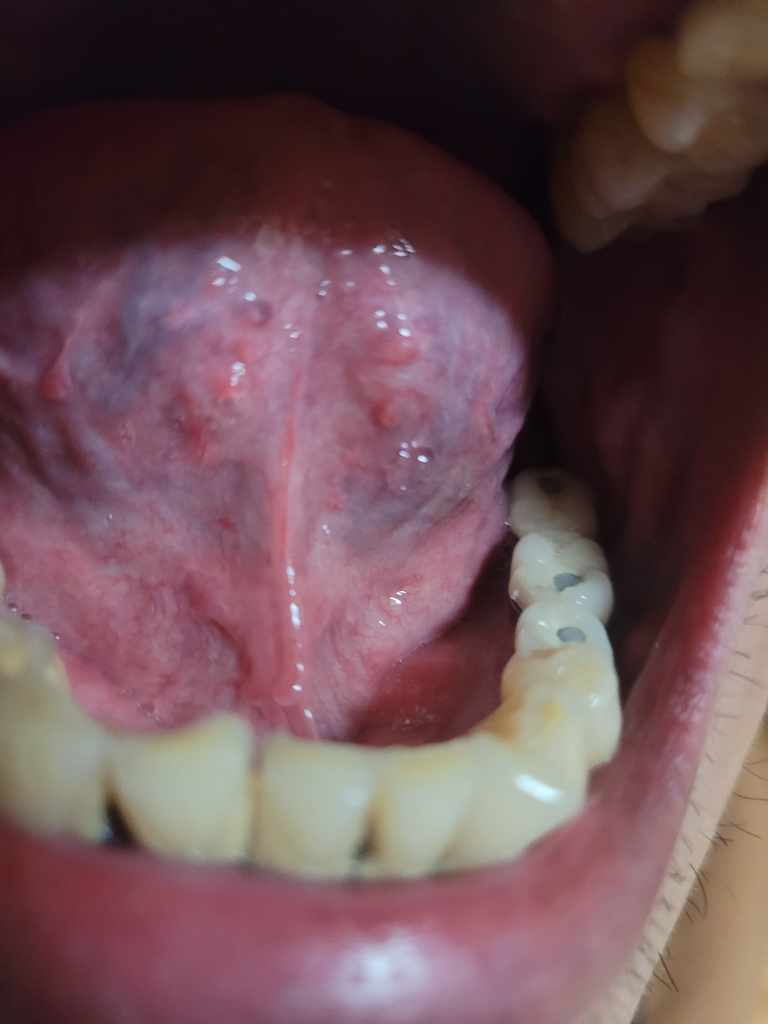

사진상으로는 구내염일 가능성이 높으나 우선 보다 정확한상태한 파악을위해 빠른 시일내에 치과를 방문하여 진료를 받으시길 권장드립니다.

사진상으로 보아서는 정확한 판단이 어렵지만 단순 구내염일 가능성이 가장 높아 보입니다. 단순 구내염이라면 보통 큰 치료없이 2주 안에 정상적으로 회복되며 불편감도 사라집니다. 다만 2주가 지났는데도 지금의 병소 부위가 계속 나타나고 그 범위가 넓어진다면 이때는 반드시 치과 방문 후 감별진단을 받아보셔야 하며 필요시 조직검사도 하셔야 합니다.

아닙니다. 혀 밑에 혈관들이 보이는겁니다. 걱정할문제는 아닙니다.

혀의 아래에 보이는 어두운색은 정맥혈관이 있어서 정맥혈이 비춰보이는 것이기 때문에 큰 문제는 아닙니다.

혀의 옆면에 치아로 인해서 손상을 받아 혈액이 안에 차있는 작은 혈액종이 있는것으로 보입니다.

이런 혈액종은 간단하게 제거할수 있지만 치아에 힘이 많이 들어갈때 생기는 경우가 있기 때문에 치아에 들어가는 힘을 줄여주는 것이 좋습니다 .

구내염 가능성이 있습니다.

구내염의 원인은 스트레스, 피로, 호르몬 변화, 비타민 B12 결핍, 철분과 엽산 결핍, 면역력 저하 등이 있습니다.

구내염의 증상은 입 안이 따갑고 화끈거림, 음식을 섭취시 통증을 호소, 구취를 유발합니다.

구내염의 치료법으로는 항바이러스제, 항진균제, 항생제, 부신피질호르몬제, 면역억제제 등의 약물치료, 구강위생, 영양개선, 스트레스 경감, 레이저치료 등이 있습니다.